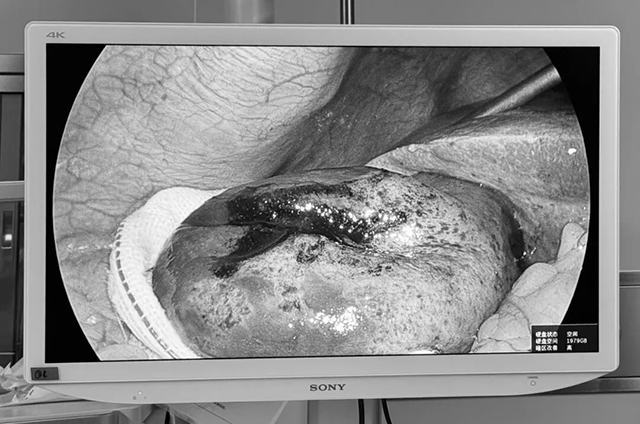

术中,腹腔镜探入之处令人心惊:那颗小结石,已牢牢嵌顿于胆囊颈部,导致胆汁完全淤阻。更可怕的是,胆囊因极度肿大、缺血,已发黑、坏疽,甚至穿孔破裂,大量脓液正不断由此流入腹腔,引发了严重的腹腔感染,周围组织水肿、粘连严重。

△坏疽的胆囊

王小林主任当机立断,凭借精湛技术精细解剖,将已丧失功能的坏疽胆囊完整切除,又以大量生理盐水反复冲洗腹腔,将每一处感染的“火种”彻底清除,留置腹腔引流管,辅以强效抗感染治疗。经过惊心动魄的救治,一场生命竞速,至此方告一段落。